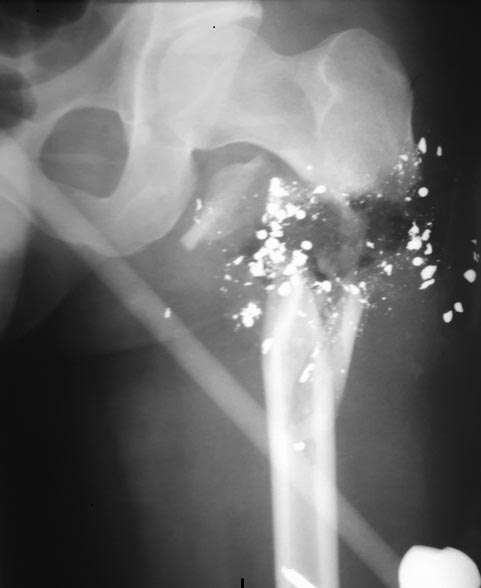

Коллеги доброго времени суток! Поступил пациент с огнестрельной раной

В/3 бедра с повреждением СНП, открытым переломом В\3 бедра с дефектом

кости. При поступлении - ПХО пластика артерии аутовеной, стабилизация

перелома стержневым аппаратом таз - бедро. На сегодняшний день -

пластика артерии состоятельная, конечность живая. На месте выходных

отверстий - рана 10+5 см по наружной поверхности В/3 бедра без признаков

воспаления. Имеется дефект кости в подвертельной зоне до 3 см. Вопрос к

уважаемому сообществу - как бы Вы поступили в данном случае? Аппарат

Илизарова? Штифт? Пластина? Одномоментно удлинить бедро и синтез?

Этапное удлинение в аппарате с последующим синтезом. Или острое

укорочение и остеосинтез до консолидации с последующим удлинением? Спасибо